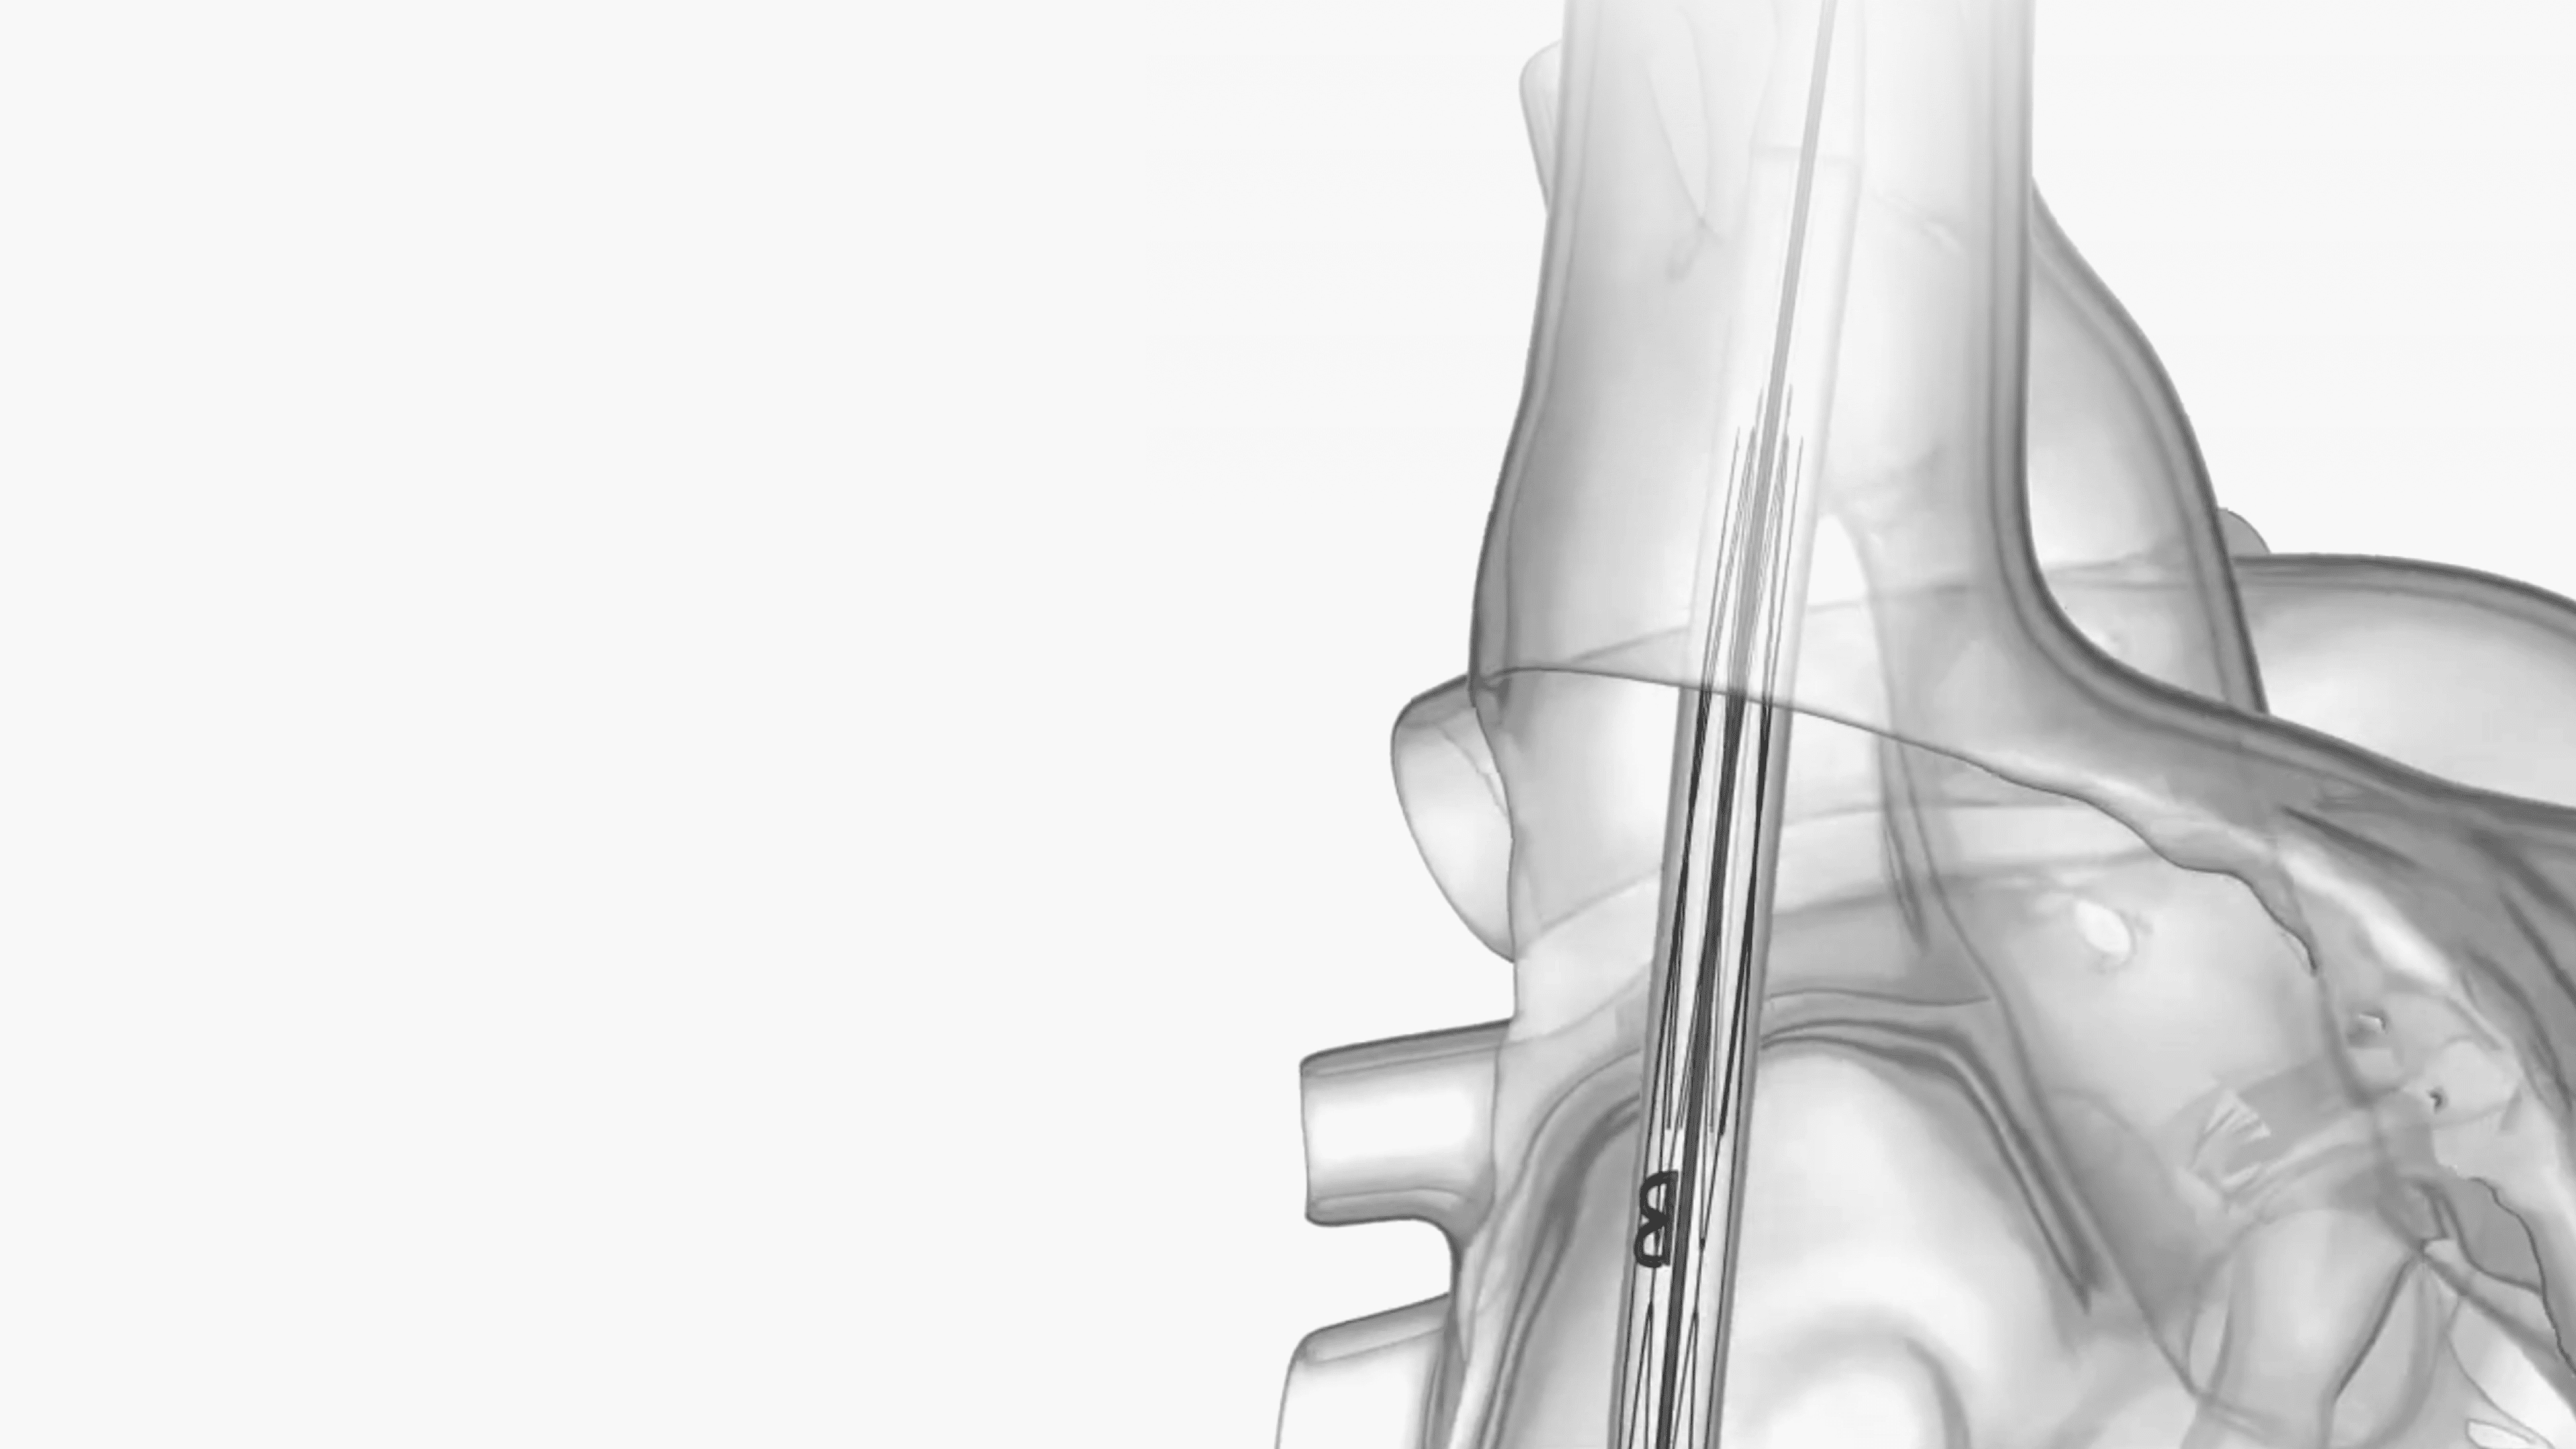

Short Implantation

Procedure

Device time of less

than 10 minutes

Secure Positioning

Engineered for

highly reliable

migration resistance

Reliable Sealing

Preventing caval

backflow while allowing

hepatic vein inflow

Mechanically Durable

Designed and tested for

600M cycles with no

fractures or malfunctions

Conscious Sedation

No need for TEE or

general anesthesia (GA)